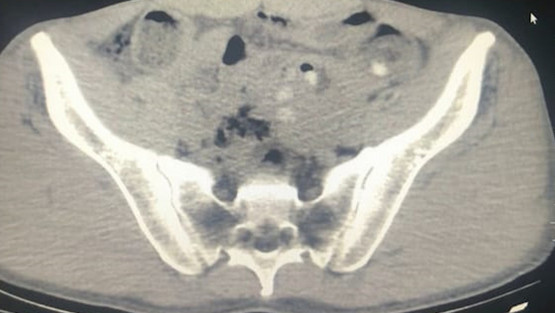

Gözaltına alınıp hastaneye götürülün şüphelilerin çekilen röntgenlerinde de midelerinde 45 kapsül metamfetamin tespit edildi.